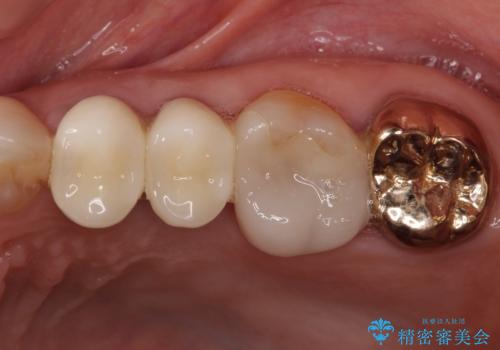

金属の縁が見えてしまったクラウン オールセラミッククラウンで審美的に